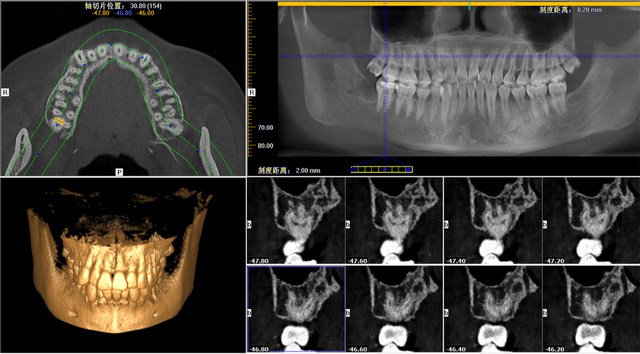

拔牙之前,傅呂通過口腔CT,告知明女士右邊上面智齒爛的很深,需盡快拔除。不僅如此,口腔CT還提示明女士該智齒有四個(gè)又彎又細(xì)的牙根,牙根離上頜竇非常近,斷根及斷根掉落上頜竇的風(fēng)險(xiǎn)較大,完整拔出來難度很大。

明女士口腔CT圖